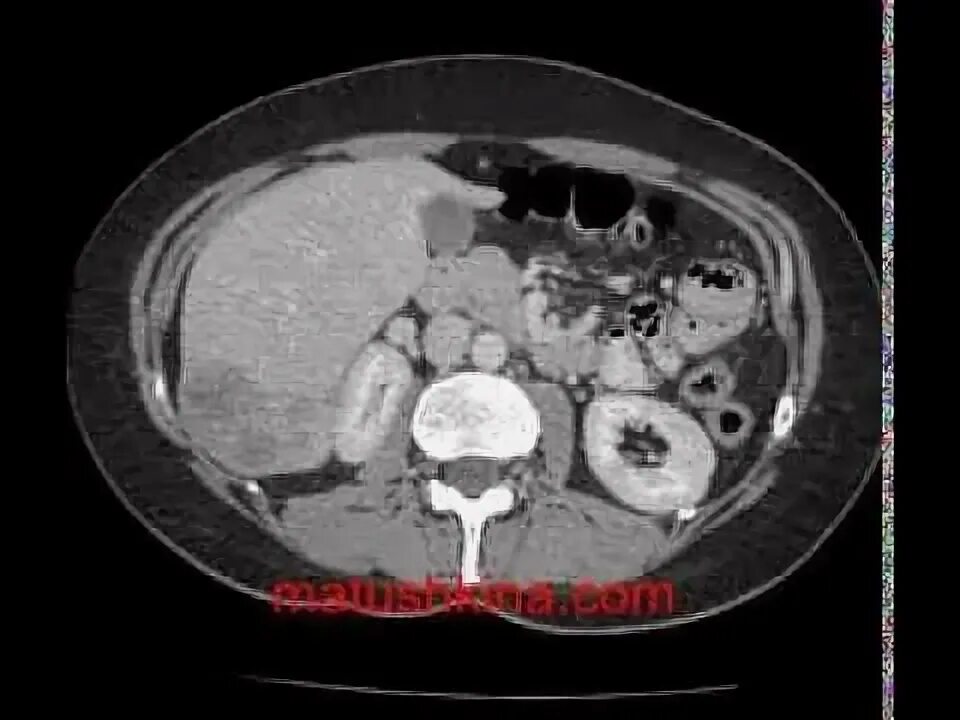

Рак прямой кт